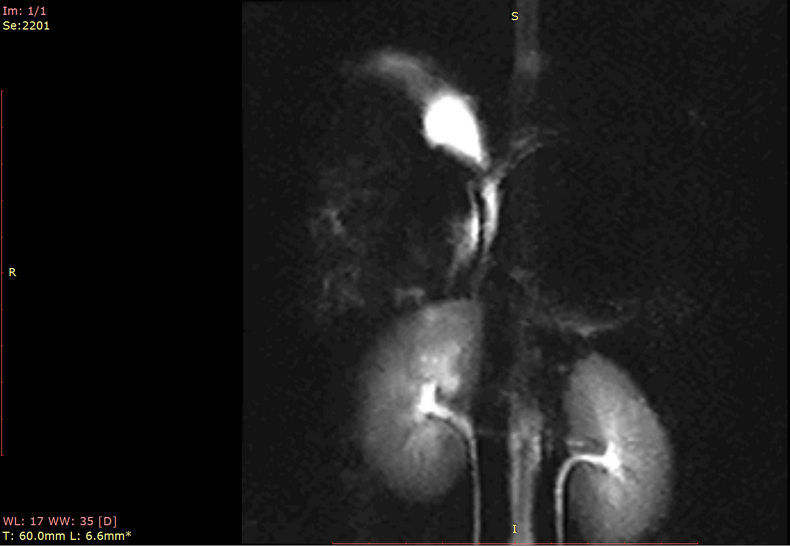

预定本数据集为2023年中国科学院昆明动物研究所实验动物中心采集6只北平顶猴(青年,雌性3只6-8岁,雄性3只7-9岁)的腹部核磁共振扫描数据,主要扫描序列包括T1w、T2w等。通过该数据可进一步了解到健康青年北平顶猴腹部影像学特征,并为未来的研究提供重要的依据。

a.物种:北平顶猴

样本数量:6只

年龄分布:6-9岁

重量分布:5-9kg

性别分布:雌性3只,雄性3只

扫描仪类型:联影uMRNX 3.0T磁共振扫描仪器

线圈:超柔线圈

麻醉程序:丙泊酚维持麻醉

扫描体位:仰卧位